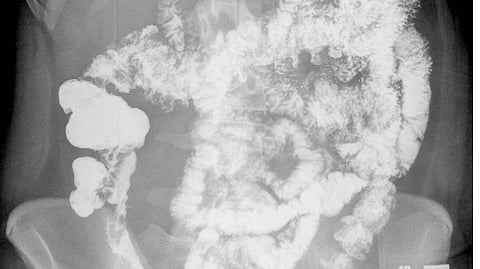

IBD, a disease category that includes Crohn’s disease and ulcerative colitis, is an autoimmune disorder marked by immune system cells that overreact and attack healthy tissue. The process results in chronic inflammation of the gut, abdominal pain, diarrhea, weight loss and rectal bleeding. Current treatments rely mostly on anti-inflammatory drugs such as steroids, along with other immune system suppressors, diet and lifestyle changes, or surgery to remove or bypass diseased intestinal tissue. However, many people with IBD experience debilitating symptoms even with treatment.